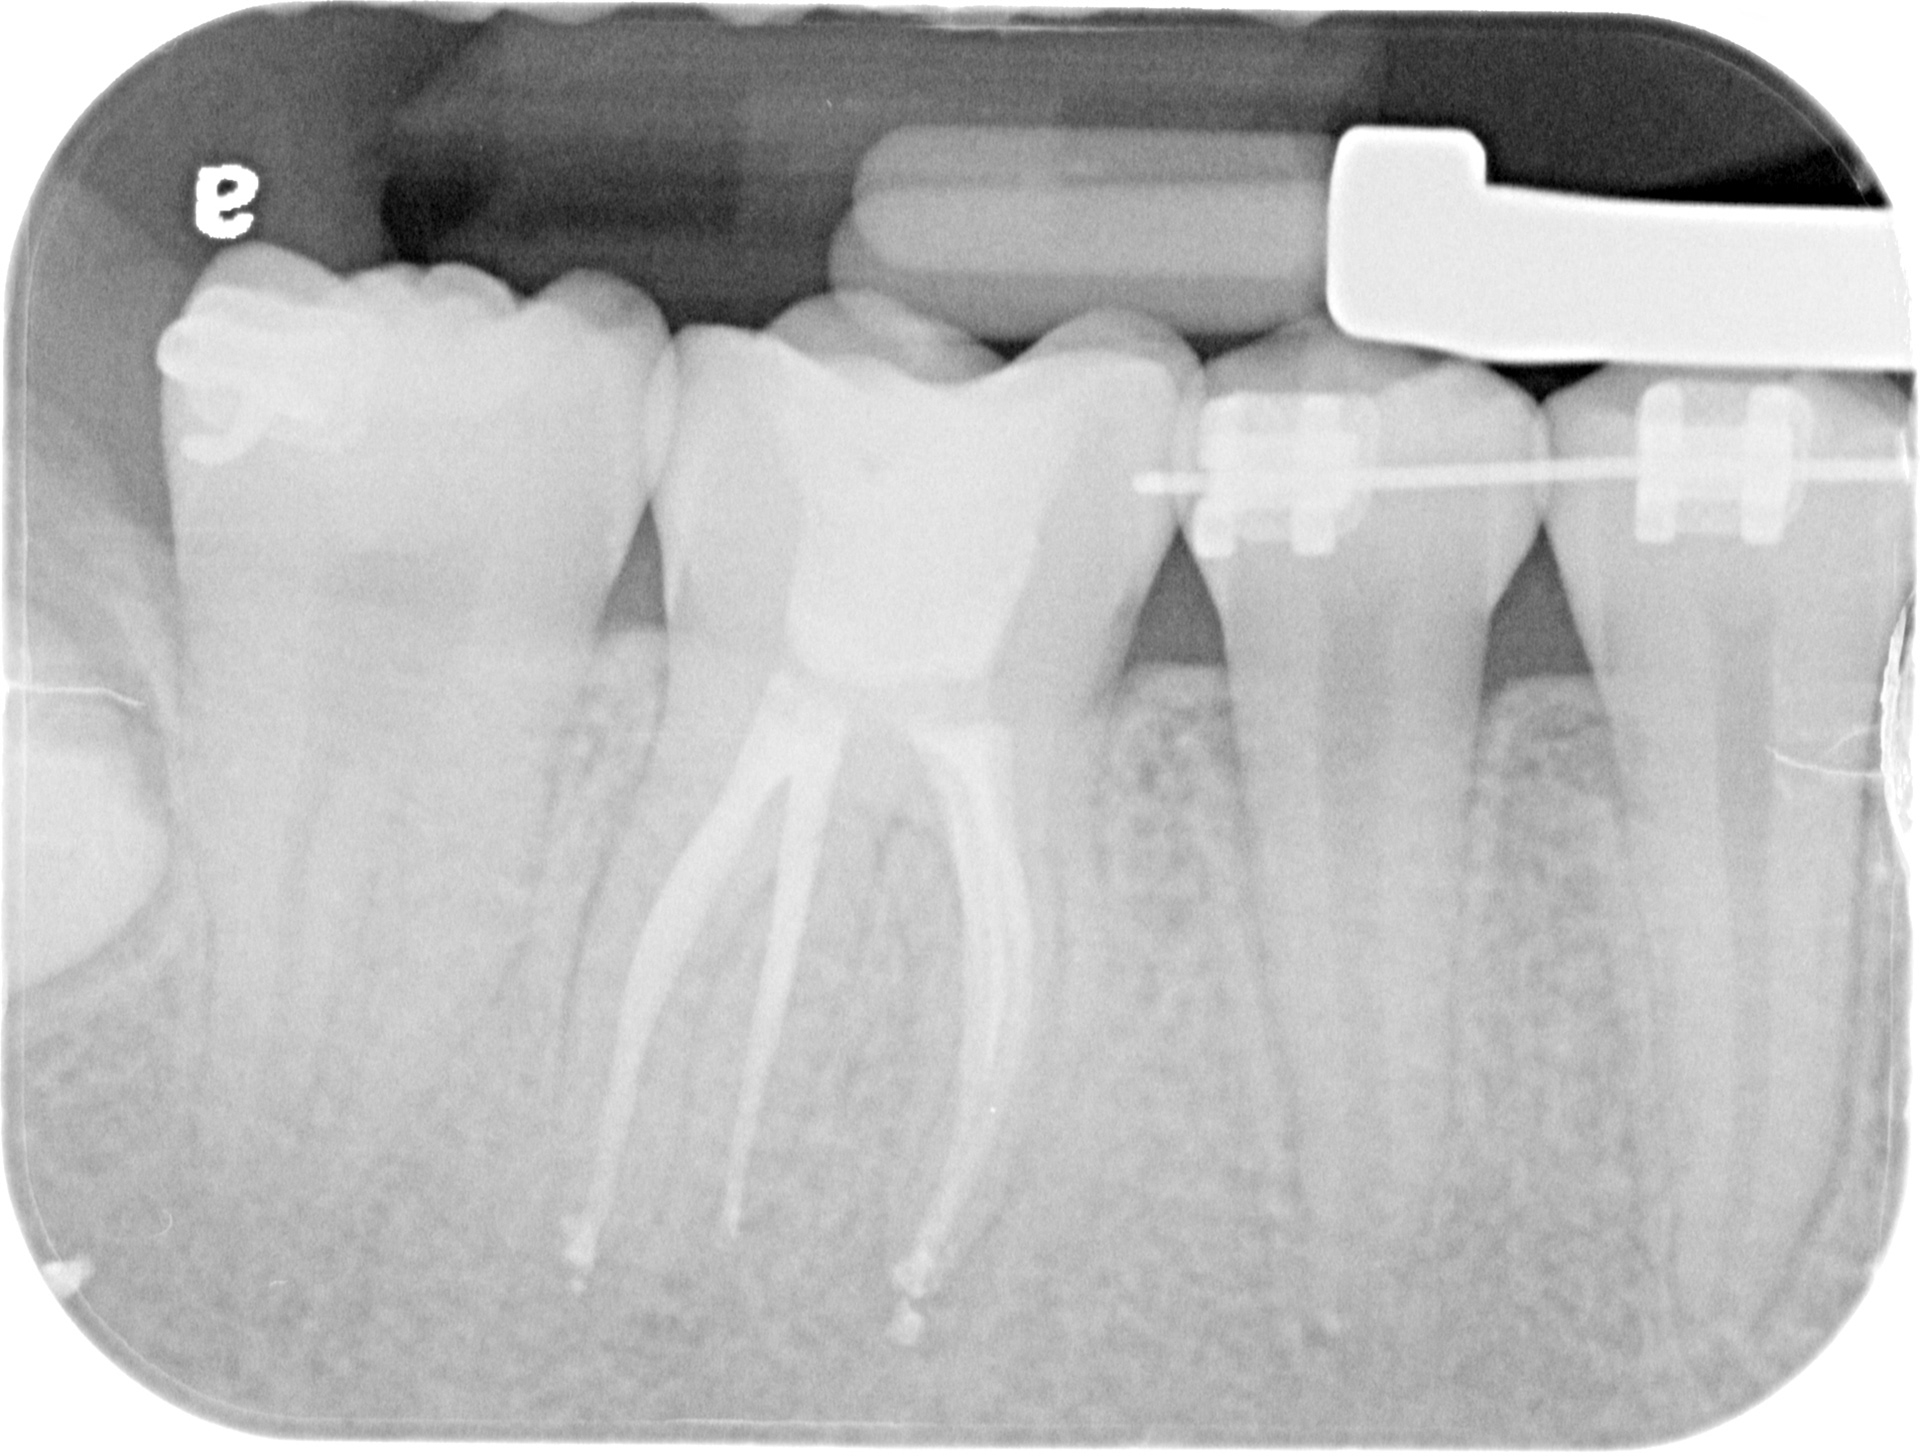

16 WITH PARTIALLY CALCIFIED CANALS

INITIAL

CANAL NEGOTIATION

WORKING LENGTH PATTENCY

FINAL